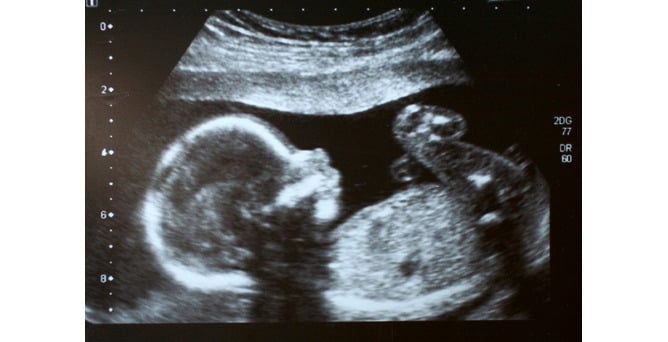

During pregnancy, it is only natural that parents want to know if their baby is growing normally, as well as keeping track of their little one's measurements and how he or she may look. Periodic appointments and checks are exactly what this is all about. The weight and length of the foetus measured by ultrasound, and are two of the parameters that can indicate whether baby is developing properly.

Two routine ultrasound scans are performed during pregnancy. The first, often referred to as the obstetric scan, is carried out by the end of the first trimester, and measures the cranio-sacral length , or in other words, the distance between the head and the sacrum. At this stage, it is not yet possible to measure the total length of the foetus, as he or she is curled up. From the fourteenth week onwards, the second ultrasound can be performed (the morphology scan), which allows the length of the foetus from head to heel to be measured, as well as the length of the humerus and the femur.

If you want to find out the foetal length without waiting for your next ultrasound, you can use an online calculator, entering the length of the femur as measured in the most recent ultrasound scan into the calculation system. The foetal length is approximately 7 times that of the femur. The foetal weight is calculated using the distance between the ears – or biparietal diameter – and the circumference of the abdomen. In both cases, the results are approximate.